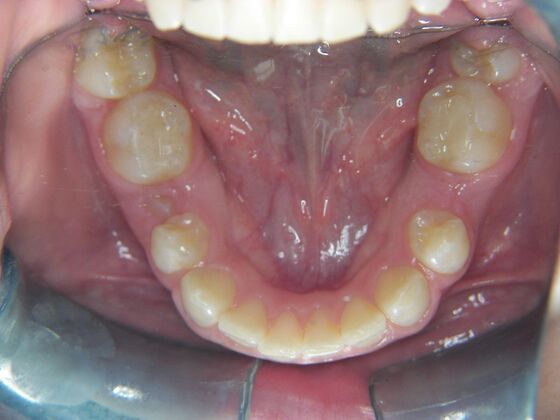

Orthodontics: Case 2

Description

Patient is 9 years old and presents with 100% overbite and blocked out upper and lower lateral incisors. Both upper central incisors are palatally inclined causing a lack of space available for most anterior teeth. Advised her parents that she needs Phase I Interceptive Orthodontic treatment to provide room for all upper and lower front teeth. Phase I treatment was begun and finished, then began Phase II treatment shortly thereafter to finalize case. Removable retainer were fabricated for retention.